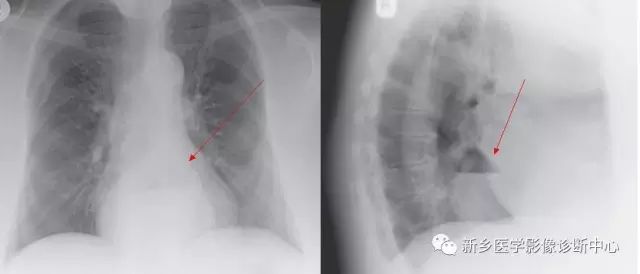

[影像描述]

CT:贲门级部分胃体组织通过食管裂孔进入胸腔内,位于膈上,其上段食管明显扩张。

食管裂孔疝

食管裂孔疝是指腹腔内脏器通过膈食管裂孔进入胸腔的疾病,疝入的脏器多为胃,为膈疝最常见的一种。多见于老年人,老年人生理各项机能减退,容易导致食管裂孔扩大、胃和食管固定不牢。

CT:食管裂孔疝以食管下端纵隔内有疝囊检出为直接征象。疝囊以假肿块样改变为特征,可有软组织密度肿块,也可表现为囊性液体密度影,部分疝囊以食管下端扩张改变为影像表现,经食管裂孔向膈下胃腔延续为主要特点。疝囊外壁光整,内壁可呈锯齿状,可见胃黏膜影像。胃壁充盈好则厚度较薄,疝囊带状管腔扩张样改变,内有潴留食物;充盈不佳者囊壁较厚,表现为软组织团块样影,内有少量液体或气体影。采用CT增强扫描,胃壁与疝囊囊壁均匀一致。